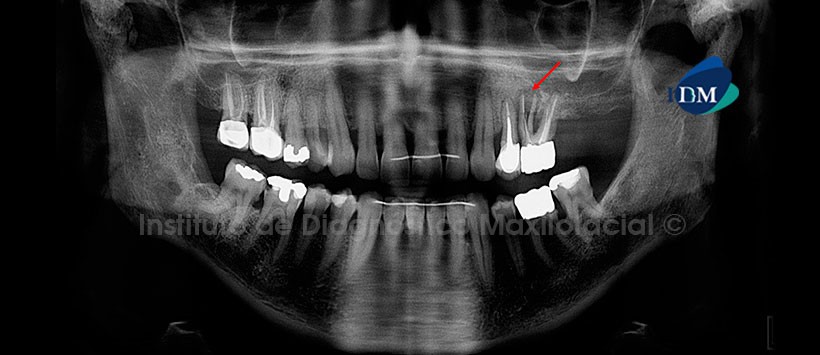

Paciente femenino de 55 años de edad que es referida por presentar dolor en la pieza 26. La radiografía panorámica nos muestra un trazo de fractura vertical en la raíz mesial de la pieza 26 que condiciona la separación y divergencia de los segmentos. Así mismo, se observa el material de obturación parcial de conductos y la presencia de un proceso osteolítico perirradicular. Por otro lado, se aprecia la alteración de la morfología de ambos cóndilos mandibulares, múltiples restauraciones coronarias, obturación de conductos radiculares, dispositivos radiopacos de fijación en el sector anterior y dilaceración radicular de la pieza 48 (Fig. 1).